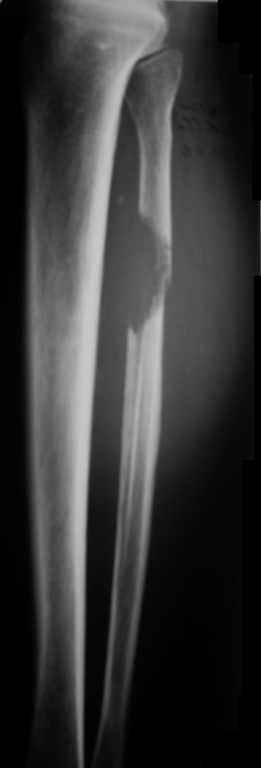

Ещё одно клиническое наблюдение - лимфома кости, до и после ПХТ и лучевой терапии.